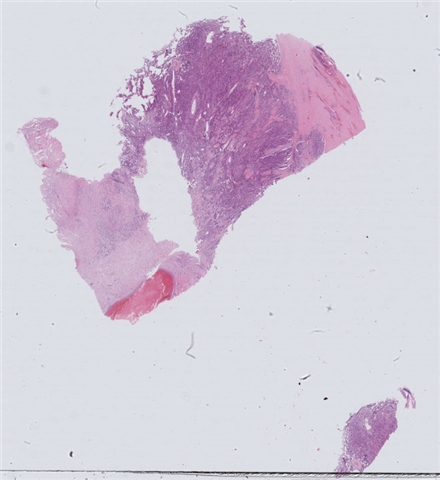

性别:       年龄:41

患者详情: 患者诉1天前无明显诱因出现脐周腹痛,持续性钝痛,不向远处部位放射,进食后感恶心,无呕吐,无发热、腹泻等不适,后腹痛逐渐转移至右下腹,遂来我院诊治,门诊拟“急性阑尾炎”收住入院,临床拟急性阑尾炎行手术切除。

大体所见: 阑尾一条,长4.0厘米,管径0.7-0.9厘米,浆膜面灰白色、附有脓苔。

免疫组化: 肿瘤细胞:CDX-2(+)、CEA(+)、CK(+)、ECD(+); P53(+),SATB-2(+),CD56(少量+),CgA(-),syn(+)